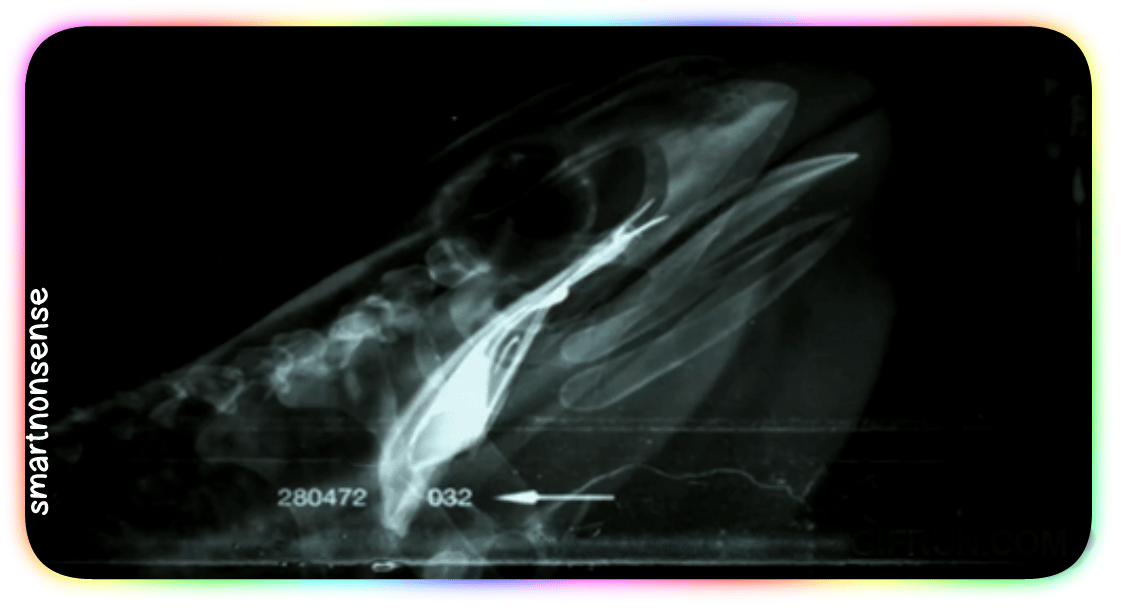

Cleaner angle:

Check out this X-ray:

BANG.

When you go to swallow that fly, your eyeballs (which – you know – usually just sit in their sockets)

Get PULLED down by muscles

Into your skull!

They press HARD on the roof of your mouth:

Driving that meal straight down your throat!